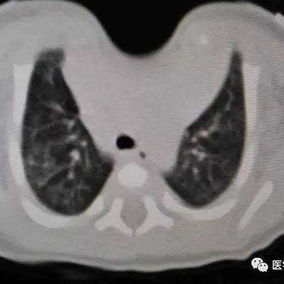

The patient was a one-month-old infant who was discovered to have an abnormality in the anterior chest wall shortly after birth. Specifically, there was a pronounced depression in the midline of the upper chest wall where the protection of bone structures was noticeably absent. The infant was diagnosed with sternal cleft and congenital heart disease. Due to the infant's poor health, surgical intervention has been postponed temporarily. Over time, the infant's condition gradually worsened, resulting in breathing difficulties and triggering a lung infection.

There is a noticeable depression in the center of the chest wall, accompanied by obvious paradoxical respiration. This area shows large-scale deficiency or absence of bone structures, with only about 1 cm of bone structure remaining at the inferior end of the sternum, connecting both sides of the chest wall. Additionally, the patient suffers from congenital heart diseases, including ventricular septal defect and patent foramen ovale, which have led to abnormal heart rhythms and sinus tachycardia.